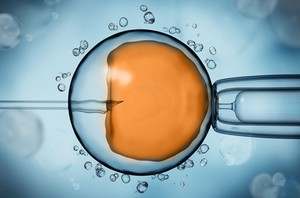

Fait partie de la PMA ou de l’AMP (Assistance médicale à la procréation) toute technique permettant la procréation en dehors du processus naturel résultant d’un rapport sexuel entre un homme et une femme. La liste de ces techniques est fixée par arrêté du ministre chargé de la santé après avis de l’agence de la biomédecine (Code de la santé publique, art. 2141-1).

- La fécondation in vitro (FIV) d’un ovule par un spermatozoïde hors du corps de la femme, dans l’éprouvette du biologiste, avec transfert d’embryon frais ou après congélation, avec ou sans donneur de gamètes extérieur au couple ;

- L’insémination artificielle (IA) qui consiste à déposer les spermatozoïdes du conjoint (IAC) ou d’un donneur (IAD) au niveau du col de l’utérus ou dans la cavité utérine pour qu’il ait fécondation naturelle d’un ovocyte dans le corps de la femme.

En France, en 2018, 1 enfant sur 40, soit 2,5 % des naissances a été conçu grâce à une technique de la PMA, qu’il s’agisse d’une FIV ou d’une IA, avec une dominance de la FIV qui représente 70 % des enfants nés à l’aide d’une PMA.